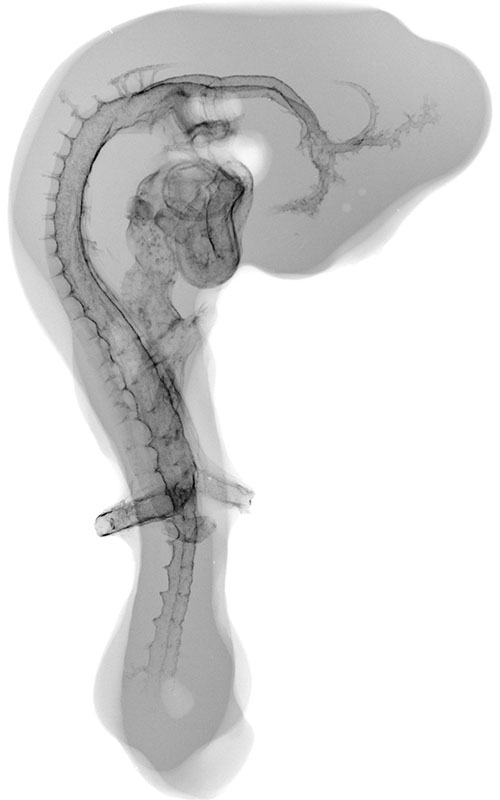

Chick Embryo Microangiography

The Chick Embryo Microangiography website is a collection of micrographs depicting the vasculature of chick embryo development from day 2.5 to day 9. The chick typically hatches at day 21. Days 2.5 to 9, as represented in this collection, correspond to Hamburger-Hamilton (HH) stages 16 to 35. Hatching typically occurs at HH stage 46. The collection of images is intended to serve students, researchers, and the general public interested in viewing, studying and teaching animal development.

Composite Image of numerous chick embryo x-ray micrographs